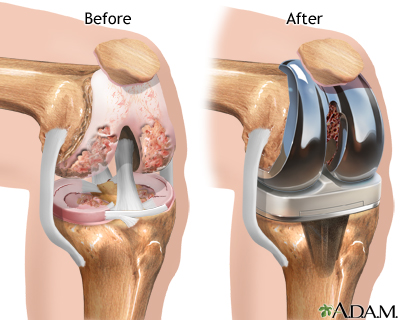

Knee joint replacement is a surgery to replace a knee joint with a man-made artificial joint. The artificial joint is called a prosthesis.

Damaged cartilage and bone are removed from the knee joint. Man-made pieces are then placed in the knee.

These pieces may be placed in the following places in the knee joint:

- Lower end of the thigh bone -- This bone is called the femur. The replacement part is usually made of metal.

- Upper end of the shin bone, which is the large bone in your lower leg -- This bone is called the tibia. The replacement part is usually made from metal and strong plastic.

- Back side of your kneecap -- Your kneecap is called the patella. The replacement part is usually made from a strong plastic.

Most artificial knees have both metal and plastic parts. Some surgeons now use different materials, including metal on metal, ceramic on ceramic, or ceramic on plastic.